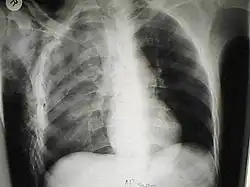

Signs and symptoms of spontaneous subcutaneous emphysema vary based on the cause, but it is often associated with swelling of the neck and chest pain, and may also involve sore throat, neck pain, difficulty swallowing, wheezing and difficulty breathing.[5] Chest X-rays may show air in the mediastinum, the middle of the chest cavity.[5] A significant case of subcutaneous emphysema can be detected by touching the overlying skin, which will feel like tissue paper or Rice Krispies.[8] Touching the bubbles causes them to move and sometimes make a crackling noise.[9] The air bubbles, which are painless and feel like small nodules to the touch, may burst when the skin above them is palpated.[9] The tissues surrounding SCE are usually swollen. If large amounts of air leak into the tissues around the head, the face can swell considerably.[8] In cases of subcutaneous emphysema around the neck, there may be a feeling of fullness in the neck, and the sound of the voice may change.[10] If SCE is particularly extreme around the neck and chest, the swelling can interfere with breathing. The air can travel to many parts of the body, including the abdomen and limbs, because there are no separations in the fatty tissue in the skin to prevent the air from moving.[11]

Significant cases of subcutaneous emphysema are easy to diagnose because of the characteristic signs of the condition.[1] In some cases, the signs are subtle, making diagnosis more difficult.[13] Medical imaging is used to diagnose the condition or confirm a diagnosis made using clinical signs. On a chest radiograph, subcutaneous emphysema may be seen as radiolucent striations in the pattern expected from the pectoralis major muscle group. Air in the subcutaneous tissues may interfere with radiography of the chest, potentially obscuring serious conditions such as pneumothorax.[18] It can also reduce the effectiveness of chest ultrasound.[28] On the other hand, since subcutaneous emphysema may become apparent in chest X-rays before a pneumothorax does, its presence may be used to infer that of the latter injury.[13] Subcutaneous emphysema can also be seen in CT scans, with the air pockets appearing as dark areas. CT scanning is so sensitive that it commonly makes it possible to find the exact spot from which air is entering the soft tissues.[13] In 1944, M.T. Macklin and C.C. Macklin published further insights into the pathophysiology of spontaneous Macklin's Syndrome occurring as a result of a severe asthmatic attack.